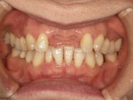

50代女性

歯がこのままではダメだと思い、一念発起された50代女性の方です。

もちろん治療期間が長期にかかることも、治療費が高額になることも、外科的な手術が何度か必要であることなど、

インプラント治療と咬み合わせ治療のほぼ全てを大名歯科ホームページで予め知っていただいた上で決心され来院されたそうです。

インプラント治療は顎骨が乏しかったため、増骨手術も併用しなければならない難症例でした。

治療期間中は残存歯数が少ない上に、丈夫でないため生活に不自由な点がでました。

さらに咬み合わせが安定しにくい症例のため、プラスチック仮歯がよく壊れたり、外れたりして、修理に来院していただくなど大変な苦労とご迷惑をおかけしました。

審美性(見た目)は十分回復できたと思っており、患者さんも大変満足されています。

食事は当然のことかもしれませんが、よく咬めるようになったそうです。

咬み合わせ治療は非常に難しいため、これで十分かどうか分かりませんが現在もこのまま定期的なメインテナンス中です。